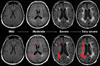

White matter disease is commonly detected on brain MRI of aging individuals as white matter hyperintensities (WMH), or 'leukoaraiosis." Over the years, it has become increasingly clear that the presence and extent of WMH is a radiographic marker of small cerebral vessel disease and an important predictor of the lifelong risk of stroke, cognitive impairment, and functional disability. A number of large population-based studies have outlined the significance of WMH as a biomarker for long-term cerebrovascular disease and dementia. In this review, we describe the conceptual framework and methodology that support this association and link the existing knowledge to future lines of investigation in the field.